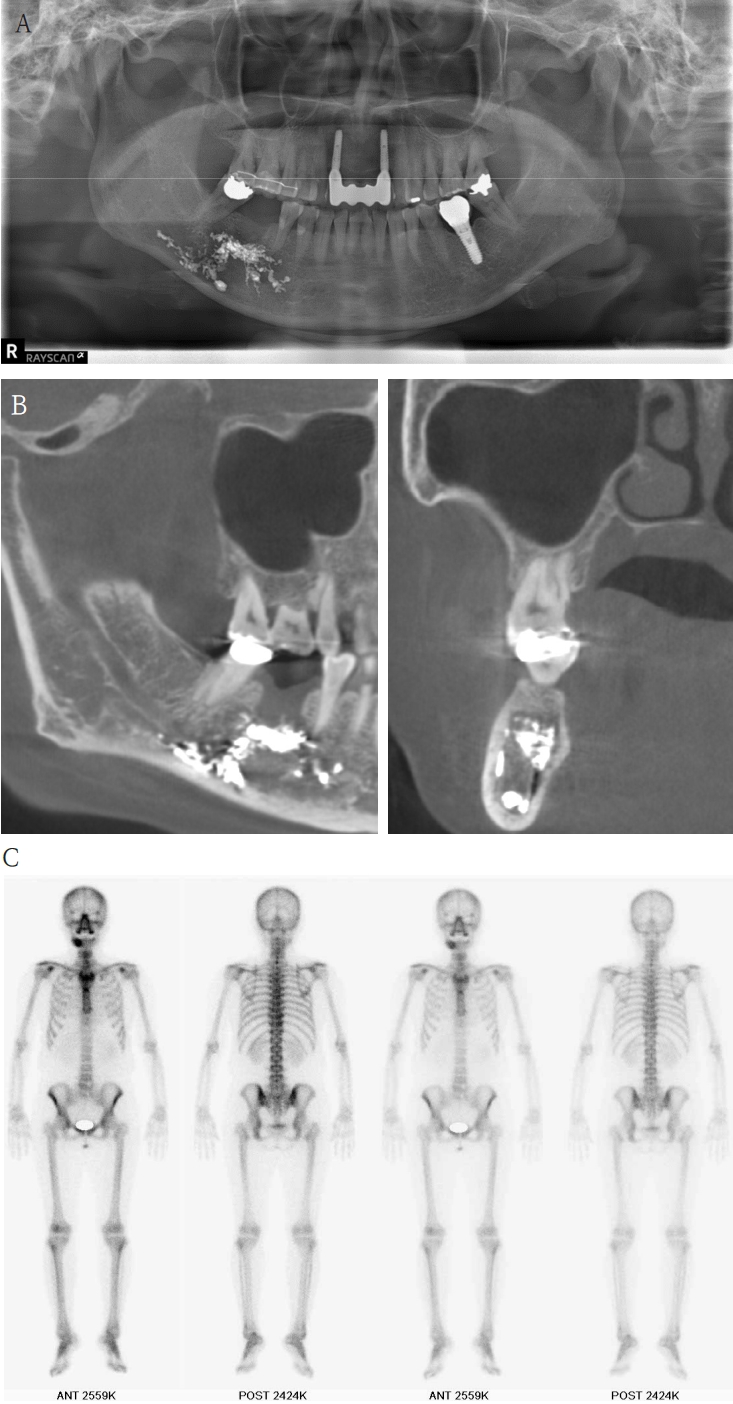

Case 3

A 61-year-old female presented with intermittent right mandibular swelling and pain after root canal therapy was done using EndoSeal MTA 5 months ago. A panoramic radiograph, CBCT and bone scan confirmed material extrusion and mild localized bone changes (Fig. 4). Initial neurologic evaluation demonstrated nearly normal sensory function, with Visual Analog Scale (VAS) 4 discomfort. Surgical curettage was performed under local anesthesia. A post-operative panoramic radiograph confirmed the substantial removal of the foreign body (Fig. 5). Postoperatively, the patient reported significant improvement at both the one- and two-month follow-ups. Due to full symptom resolution, no follow-up neurosensory testing was performed.

A. Pre-op panoramic radiograph of Case 3 patient. B. Pre-op CBCT of Case 3 patient. C. Pre-op bone scan of Case 3 patient